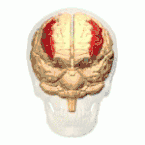

أسماء المناطق المبينة بالأرقام كما يلي:

1) القطب الجبهي ( Polus frontalis)

2) القطب القذالي ( Polus occipitalis )

3) الشق الطولاني للمخ ( Fissura longitudinalis cerebri)

4) التلفيف الجبهي العلوي ( Gyrus frontalis superior)

5) التلفيف الجبهي الوسطي ( Gyrus frontalis medius)

6) التلفيف الجبهي السفلي ( Gyrus frontalis inferior)

7) الثلم الجبهي العلوي ( Sulcus frontalis superior)

8) الثلم الجبهي السفلي ( Sulcus frontalis inferior)

9) الثلم أمام المركزي ( Sulcus praecentralis)

10) التلم المركزي ( Sulcus centralis)

11) الثلم خلف المركزي ( Sulcus postcentralis)

12) الثلم داخل الفص الجداري ( Sulcus intraparietalis)

13) الثلم الوحشي (شق سلفيوس) ( Sulcus lateralis (Fissura Sylvii))

14) التلفيف أمام المركزي ( Gyrus praecentralis)

15) التلفيف خلف المركزي ( Gyrus postcentralis)

16) الفصيص الجداري العلوي ( Lobulus parietalis superior)

17) الفصيص الجداري السفلي ( Lobulus parietalis inferior)

18) الفص القذالي ( Lobus occipitalis)

19) التلفيف الصدغي العلوي ( Gyrus temporalis superior)

20) التلفيف فوق الهامشي (؟) ( Gyrus supramarginalis)

الفص الجبهي (Frontal lobe)

الفص الصدغي (Temporal lobe)

الفص الجداري (Parietal lobe)

الفص القذالي (Occipital lobe)

الفص الحوفي (Limbic lobe)

الجَزيرَة (Insula)